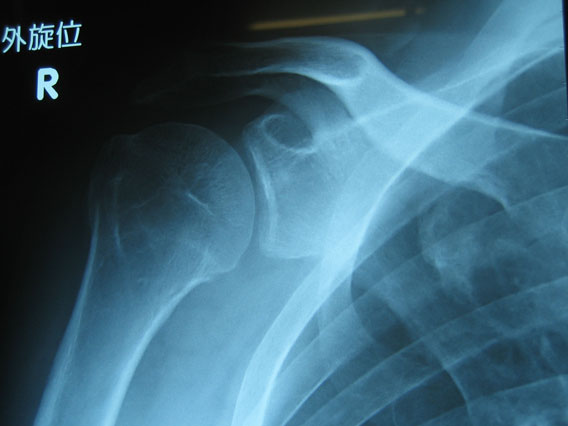

骨折のその後

1月の22日に骨折してほぼ3ヶ月なわけですが、主治医からは「あとはもう自主トレ続けてください。もっと可動域は広がるはずです。何かあったらまた来てください」ということで卒業を言い渡されました。

肩の状態はというと日常生活は全く問題がありませんが、背中を掻くとか、そういうことをしようとするとかなり不便です。泳ぎにも行ってみているわけですが、平泳ぎは全く問題ないものの、クロールはかなり難儀です。バタフライはひとかきで「無理」ということで断念しました。なので、リハビリを続けています。どうせ次の冬までは真剣にスポーツをやることはないので、のんびり治して行こうと思います。せめてバタフライはできるようになりたいなぁ。